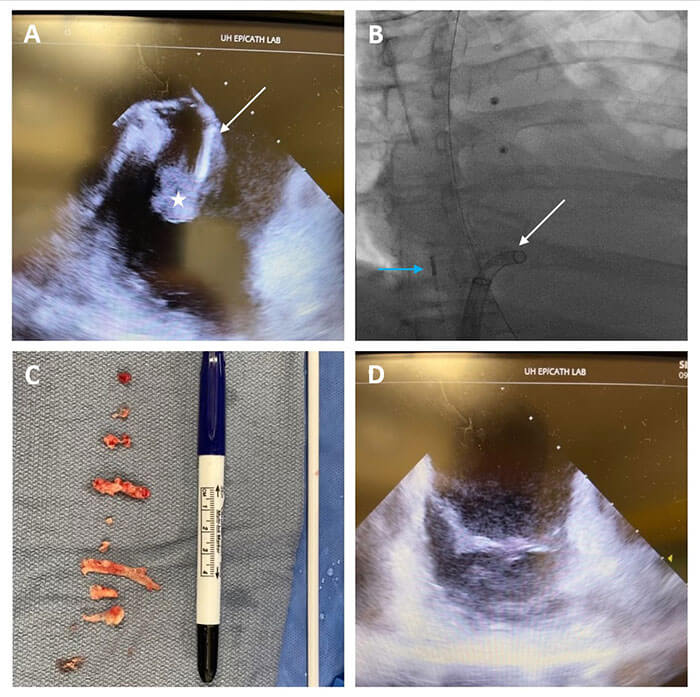

A team of interventional cardiologists and cardiac surgeons at University Hospitals Harrington Heart & Vascular Institute are the first in the U.S. to report a safer, minimally invasive strategy for removing vegetations in the heart associated with right-sided infective endocarditis – common among IV drug users, people on dialysis and people with indwelling catheters. The procedure, using the FlowTriever system with FLEX technology originally designed to treat pulmonary embolism, is conducted in the catheterization lab on an awake patient – no operating room, intubation or heart-lung bypass machine required. The novel procedure employs intracardiac echocardiography and fluoroscopy guidance, eliminating the need for uncomfortable transesophageal echocardiography for the patient.

Mehdi H. Shishehbor, DO, MPH, PhD, President of University Hospitals Harrington Heart & Vascular Institute and the Angela and James Hambrick Master Clinician in Innovation, reported the first case in the journal Catheterization & Cardiovascular Interventions. Since then, he and his team have completed an additional 13 successful cases.